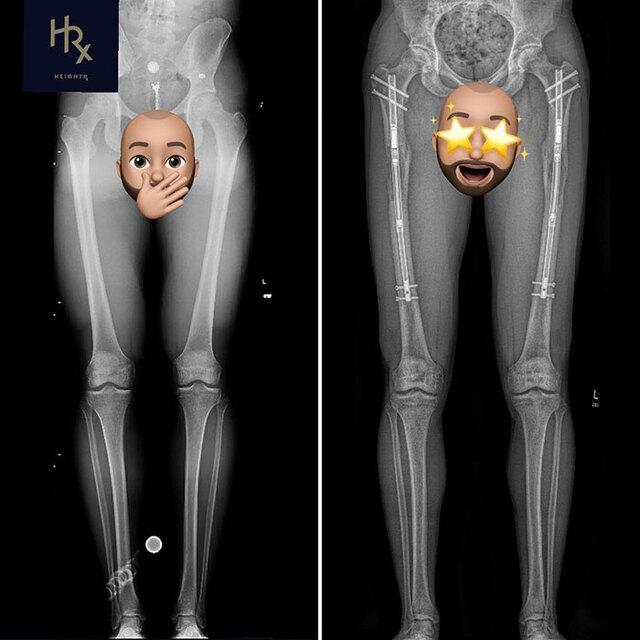

Between 2016 and 2022, Theresia made a decision that shocked many: she underwent multiple leg-lengthening surgeries, spending more than €150,400 ($162,340) to increase her height from 1.70 meters to 1.84 meters.

Theresia now finds herself longing for the day surgeons can remove the metal rods from her legs. She hopes the removal will bring relief after nearly a decade of pain, swelling, and limited mobility.